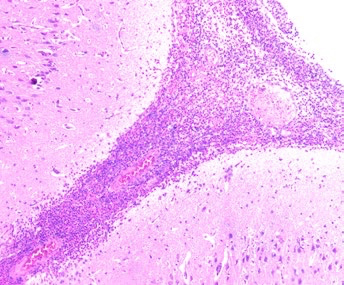

Streptococcus suis: claves diagnósticas desde la lesión hasta el laboratorio